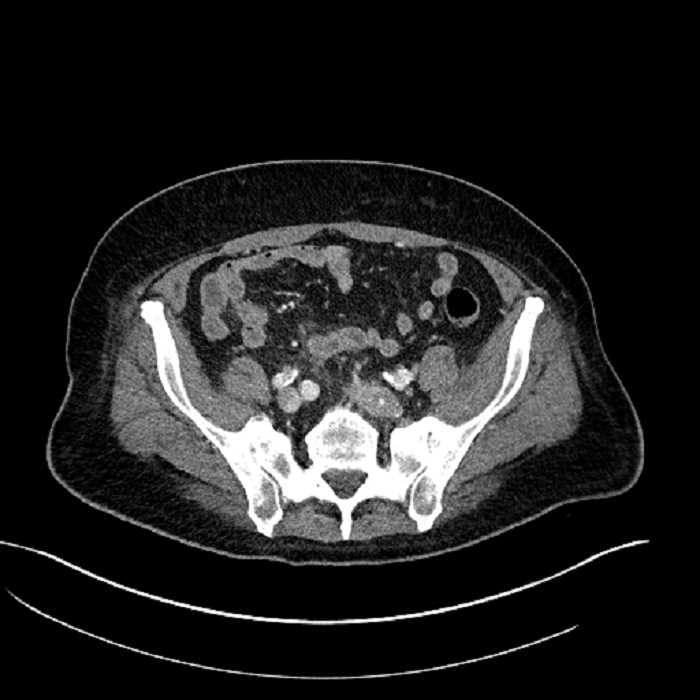

Age: 63

Sex: Male

Indication: Abdominal pain

• Mild mural thickening of a segment of the sigmoid colon with adjacent fat stranding and a 1.5 cm fluid and gas collection along the tip of an inflamed diverticulum

• Loss of the normal fat plane between this collection and adjacent loops of small bowel, which demonstrate mural thickening

• No bowel obstruction

• High grade stenosis of the left common iliac artery, with the left internal and external iliac arteries remaining patent

Acute sigmoid diverticulitis complicated by a small contained perforation and a large abscess in the right hepatic lobe. Additional small subcapsular abscesses along the anterior margin of the left hepatic lobe.

Additionally, loss of the normal fat plane between the peridiverticular collection and adjacent thickened loops of small bowel raises the potential for an enterocolonic fistula.

High grade stenosis of the left common iliac artery. The left external and internal iliac arteries are patent.

Hepatic abscess showing the double target sign with low density internally surrounded by a thin inner enhancing rim (red arrow) and ill-defined outer low density rim (yellow arrow). Blue arrow indicates an internal septation. Red arrows: additional smaller subcapsular abscesses. Red arrow: focal contained perforation associated with diverticulitis.